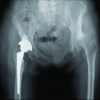

A 45-year-old female patient with polytrauma was referred to our institution with fractures of shaft femur, right clavicle, and pelvis with concomitant abdominal and chest injuries. After initial resuscitation and stabilization, the patient was operated for fracture shaft of femur and the other injuries were managed conservatively (Fig. 1 a, b, c, d, ). Postoperatively, mechanical ventilation was required, and the patient was shifted to the intensive care unit. The brachial artery was cannulated for IA monitoring of blood pressure on the left arm. Subsequently, 3 days after the cannulation, bluish discoloration of the distal end of the index finger was observed. Initially, an accidental drug injection through the arterial line resulting in ischemia was suspected. Since the patient was comatose, brachial artery cannulation on the right side was done for further monitoring. Remarkably, signs of ischemia were now noted on the right thumb 48 h after the cannulation (Fig. 2 a & b). It was confirmed that no drug was given through the cannula on this side. The coagulation profile came out to be normal. Cardiac evaluation turned out to be normal, with the absence of any source of emboli in the cardiac valves or chambers. In spite of giving heparin, papaverine, and oral anticoagulants, the digits could not be saved. Subsequently, the amputation of the digits was done.